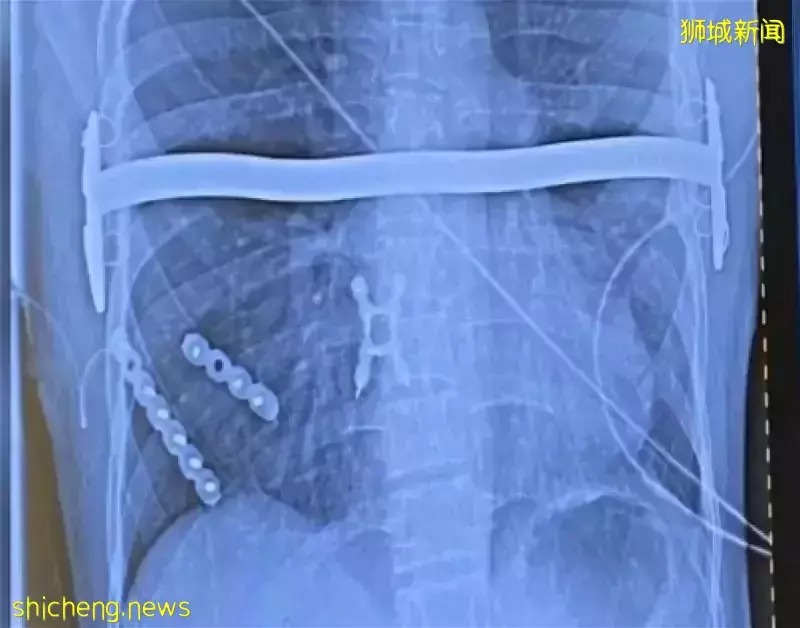

狮城医院3D打印胸腔 医治胸部畸形男子